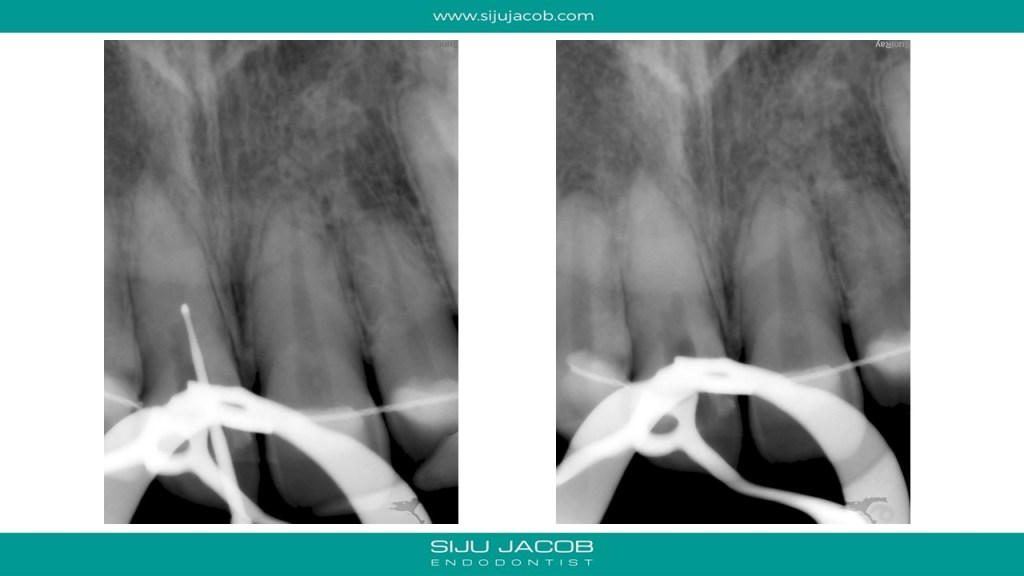

This case was calcified all the way to the apical one third. As we go deeper, the labio-palatal orientation becomes a problem and as we approach the apical part, the margin for error decreases. In this case, I took an inter-appointment CBCT to see the location of the canal. The video explains the whole process.

And here are the pics for the case: